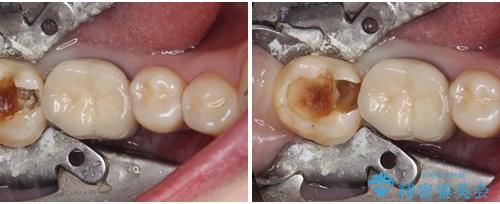

- 下顎の奥歯に頻繁に物が挟まるとのことで来院された患者様です。

最近ものが挟まりやすくなったり、冷たいものがしみるようになったりといった症状があり、診査したところ、歯質の欠損や不適修復物などが認められました。

精度の高いセラミックインレーによる修復治療を行うこととしました。